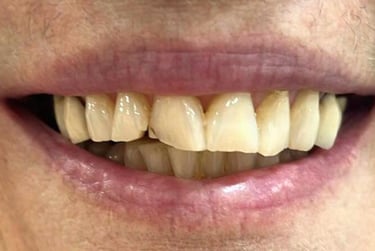

Prótese total convencional

Solução tradicional e econômica para quem perdeu todos os dentes. Embora a prótese protocolo sobre implantes ofereça mais estabilidade, a prótese total continua sendo uma alternativa acessível que devolve função e estética ao sorriso.

Antes

Depois